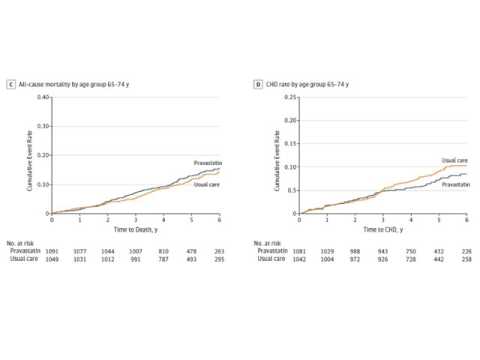

Tratamiento con estatinas. Ensayo clínico ALLHAT-LLT. Dr. Agustín Indavere. Residencia de Cardiología del Hospital C. Argerich. Buenos Aires